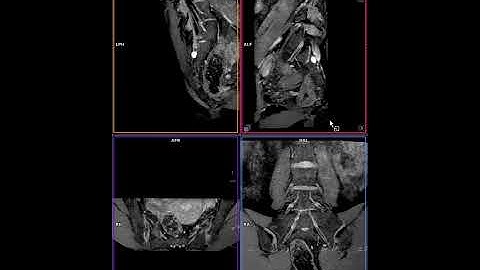

Plexus MRI – How I do it